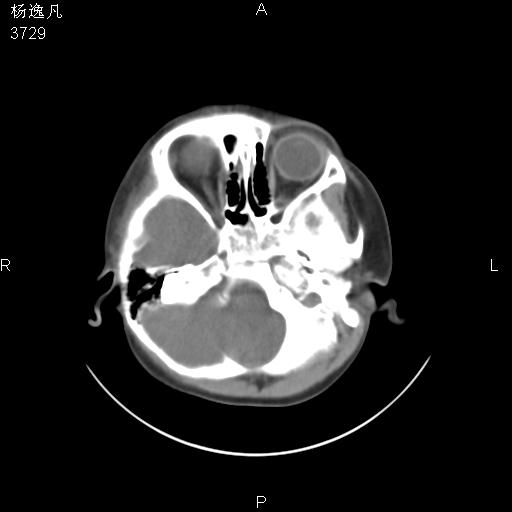

男性,5岁,面部受外伤,余无特殊

骨窗

患儿为什么做ct?腺样体肥大。

鼻咽腺样体肥大。

头颅ct平扫未见明确外伤性征象,右侧面部及颞部软组织肿胀,后鼻腔软组织影增大,增厚,鼻咽顶部变窄,考虑鼻咽腺样体增值肥厚。

还是重建了再看吧。还可以看一下始矢状位,了解一下气道的情况。